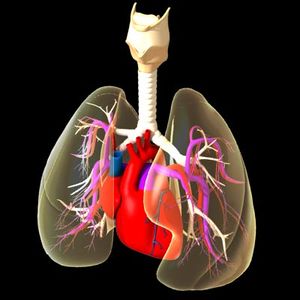

القلب Heart عضو عضلي يضخ الدم في جسم الإنسان. ومع كل دقّة يدفع القلب الدم الضروري للحياة عبر جسم الإنسان. ويحمل الدم الأكسجين والغذاء لكل خلايا الجسم وتبدأ دقات القلب ذات الإيقاع المنتظم قبل سبعة أشهر من ميلاد الطفل تقريبًا. وعندما يتوقف القلب تتوقف الحياة، إلا إذا ساعدت أجهزة آلية خاصة على دوران وأكسجة الدم. والقلب عضو عضلي مجوّف كبير، ينقسم إلى مضختين متجاورتين. وتنقل الأوردة الدموية الدم في جميع أنحاء الجسم إلى المضخة الواقعة في الجهة اليمنى التي ترسله بدورها إلى الرئتين لحمل الأكسجين، ومن ثم، ينساب الدم المؤكسد إلى الجهة اليسرى من القلب التي تضخه إلى أجزاء الجسم المختلفة بوساطة الشرايين. وهناك صمامات تتحكم في سريان الدم داخل القلب. والمضخة اليسرى، التي تدفع الدم إلى جميع أنحاء الجسم أقوى وأكبر حجمًا من المضخة اليمنى. والقلب والتشكيلات الأنبوبية الأخرى مثل الشرايين والأوردة والشعيرات تسمى جميعًا الجهاز الدوري أو الجهاز القلبي الوعائي. ينظم الجهاز العصبي عمل القلب وأجزاء أخرى من الجهاز الدوري. وينظم الجهاز العصبي التلقائي، وهو جزء من الجهاز العصبي، ضربات القلب (النبض)، فيقللها أو يزيدها حسب حاجة الجسم؛ لذلك فإن القلب يدق بصورة هادئة مثلاً عندما يكون الإنسان نائمًا ويزود الجسم بكمية قليلة نسبياً من الأكسجين. وقد تزداد سرعة ضربات القلب مرة أخرى لتزيد كمية مردود الأكسجين للجسم بغزارة. ويحدث هذا عندما يزاول الإنسان التمارين الرياضية أو عندما يصاب بالخوف أو عندما يحتاج للمقاومة أو العراك أو الجري. وقد يصيب المرض أو الخلل أي جزء من أجزاء القلب أو الأوعية الدموية، ويعتبر ذلك من الأسباب الرئيسية للوفاة في البلدان الصناعية. وأكثر أمراض القلب شيوعًا هي التي تصيب الشرايين التي تغذي القلب نفسه بالدم. والخلل الذي يصيب هذه الشرايين قد يتطور مع سنوات عمر الإنسان. فترسُّب المواد الدهنية مثلاً، يؤدي إلى انسداد شرياني وإلى قلة كمية الدم التي تزود القلب. وإذا استقبلت عضلة القلب كمية قليلة من الدم فإن هذا قد يؤثر في أدائها أو إلى موتها. ويسمى هذا الخلل أو التلف الناتج من قلة إمداد عضلة القلب بالدم النوبة القلبية. والنوبة القلبية الخفيفة قد تجبر الإنسان لكي يعيش حياة أقل نشاطًا وحركة. أما النوبة القلبية القاسية أو العنيفة فتجعل القلب غير قادر على إمداد الجسم بكمية كافية من الدم، حتى في حالة الراحة الكاملة، وقد تؤدي إلى الوفاة. وقد تصيب الأمراض أجزاء أُخرى من القلب وقد يؤدي هذا إلى تأثير مدمّر مشابه. تحققت أهم التطورات الطبية الحديثة في مجال طب القلب، وهو حقل طبي يعنى بالأمراض التي تصيب القلب والأوعية الدموية. ومنذ آلاف السنين، لم يكن مرضى القلب يعرفون أصلاً أن لهم هذه المشكلة. وفي التسعينيات من القرن العشرين الميلادي، تعلم الأطباء كيف يشخصون ويعالجون بعض حالات مرض القلب التي كان علاجها علاجها مستحيلاً في السابق، وكانت تعني الوفاة لمن يصاب بها. وأدّى اكتشاف الأدوية والتطور الهائل في الجراحة إلى إعطاء عدد من مرضى القلب أملاً في الحياة، وبدأ الأطباء بزراعة القلوب بل طوّروا أجهزة تقوم بعمل القلب مؤقتًا. واليوم تُجرى كثير من الأبحاث في علم القلب ووظائفه، ويتم التركيز على دراسة الأسباب التي تؤدي إلى أمراض القلب حتى يمكن تفاديها. وتدرس أبحاث أخرى إمكانية خفض حالات الموت والعجز التي تنتج من أمراض القلب، عن طريق دعم وتطوير أدوية وعقاقير معالجة جديدة واستحداث قلب صناعي فعّال. هذه المقالة عن قلب الإنسان بصورة خاصة، والجزء الأخير منها يصف قلب الحشرات والسمك والطيور والحيوانات الأخرى. ولمزيد من المعلومات عن عمل الدم في الجسم،

يحتوي القلب على أربعة حجيرات منفصلة تدعى: الأذينين اليمنى واليسرى والبطينين الأيمن والأيسر. تكون جدران الأذينين رقيقة نسبيا لأن طبيعة عملها الأساسي كمستودع للدم ومدخل للبطين فهي لا تقوم بعمل الضخ الأساسي الذي يتكقل به البطين. جدران البطين تكون أثخن لأنه يقوم بعملية الضخ الأساسية في الدوران الرئوي والدوران المحيطي.

تنظم حركة الدم في القلب صمامات (تدعى أيضا دسامات) تشكل بوابات وحيدة الإتجاهات تؤمن انتقال الدم من الأذينة إلى البطين ولا تسمح بالانتقال العكسي, فالتجمع الأساسي للدم الوارد للقلب يحدث في الأذينة اليمنى لينتقل بعد ذلك إلى البطين الأيمن, يقوم البطين الأيمن بضخ الدم للرئتين, يعود الدم بعد تنقيته من الرئتين إلى الأذينة اليسرى, من الأذينة اليسرى ينتقل للبطين الأيسر الذي يضخه بدوره عبر الشريان الأبهر، أو الشريان الرئيسي، إلى باقي الأعضاء.